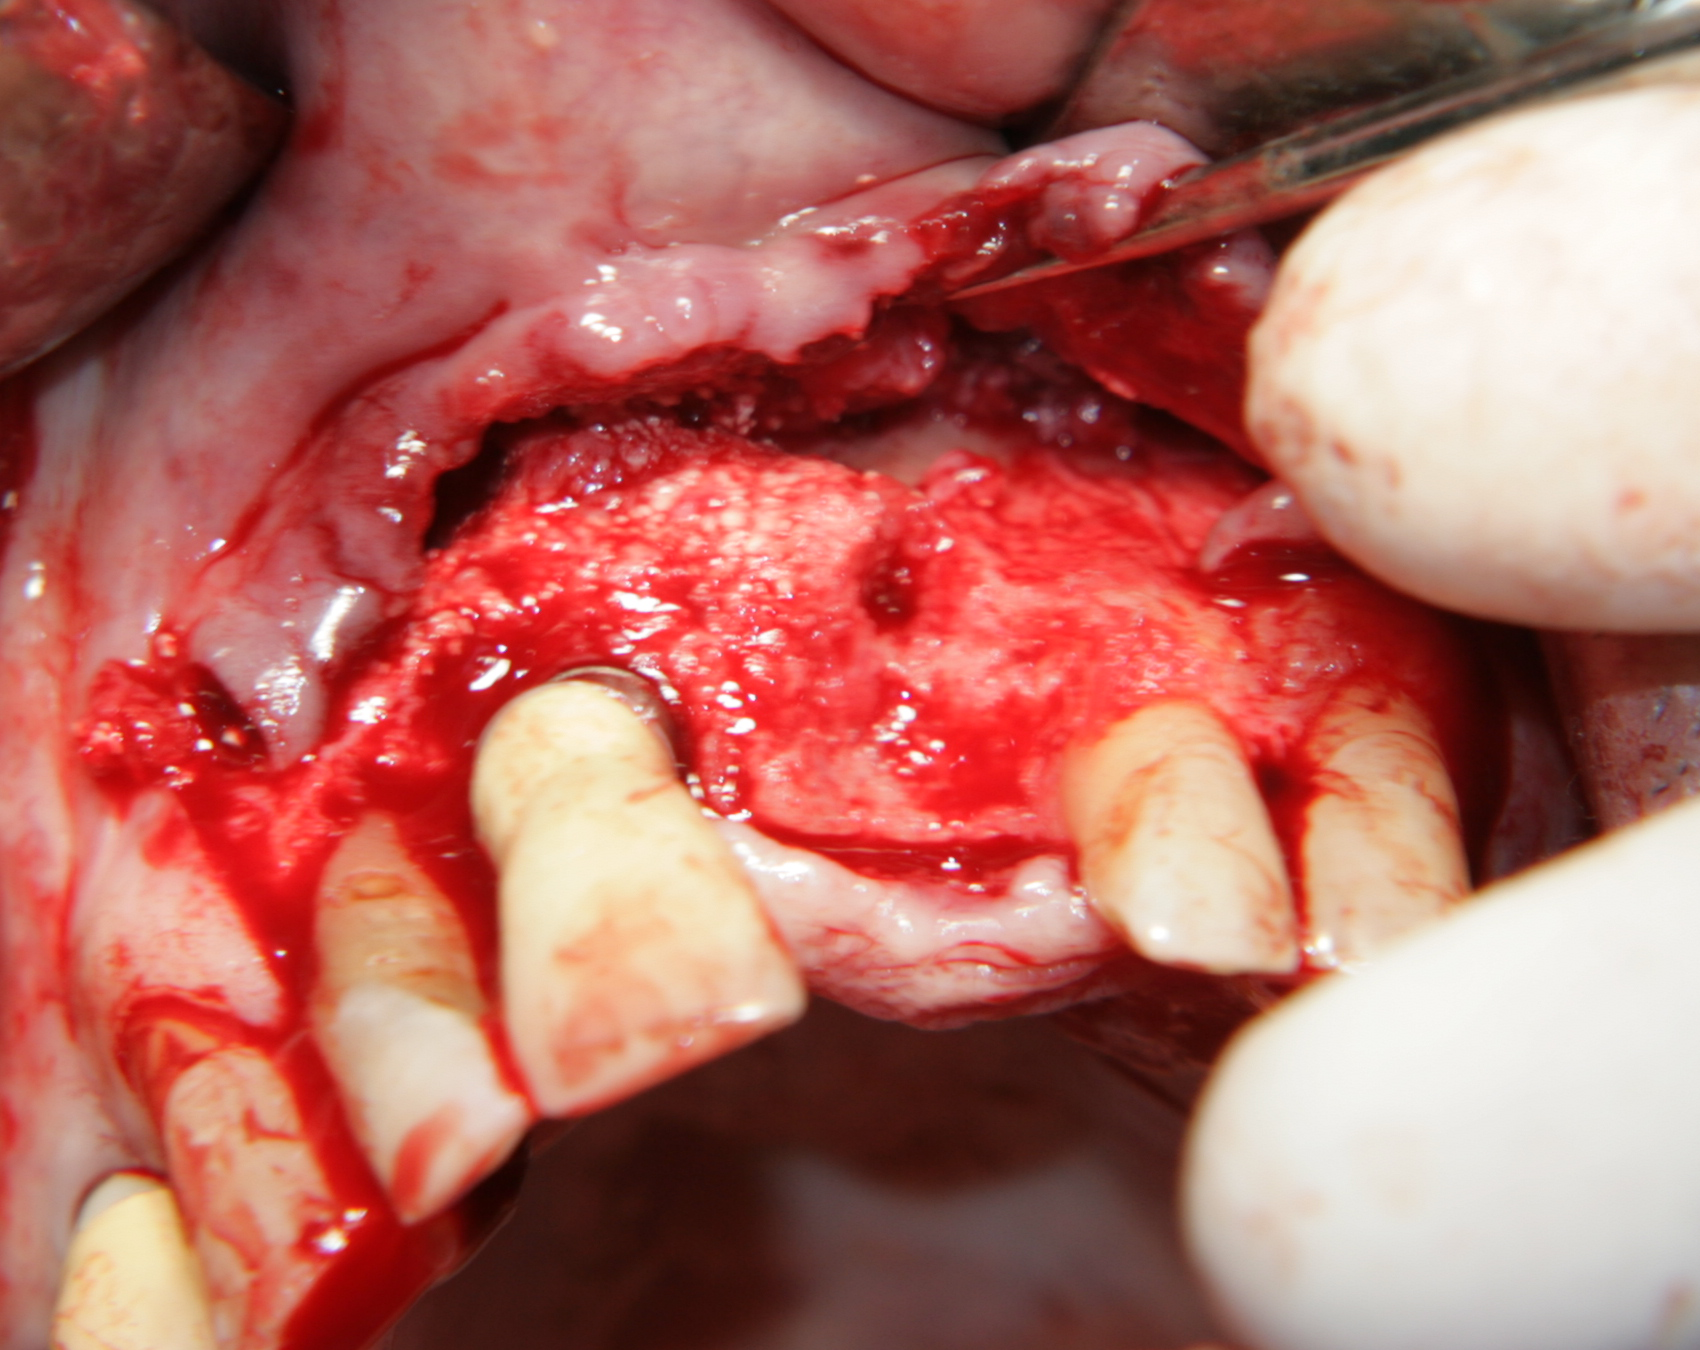

Титановите мембрани са твърди, ригидни приспособления, които се поставят в участъци с необходимост от увеличаване на костния обем - най-вече в областта на имплантологията, но също при радикуларни кисти и много рядко след екстракция на ретинирани мъдреци, при дефкетни фрактури, пострезекционни дефекти на челюстите, тежки остеомиелити и специфични възпаления на костта. Идеята на титановата мембрана е да предпази меките тъкани от колапс, поне за известен период от време, през който период под мембраната да започне костообразуване. През първите шест - осем месеца титановата мембрана оказва своя ефект, след което вече е безсмислено да остава в устата на пациента.

При операции с цел изграждане на допълнителн костна тъкан (костна пластика) винаги е добре да се перфорира кортикалната пластинка на костта. През тези перфорации излизат костни клетки, които постепенно прорастват в котозаместващия материал и синтезират нова костна тъкан. Перфорациите могат да се извършат с кръгло борче или с АСМ - фрезата на Neobiotech - Южна Корея.

С фрезата за автогенна кост се извършва много бързо и лесно отнемане на

кортикалната кост

Автогенна кост